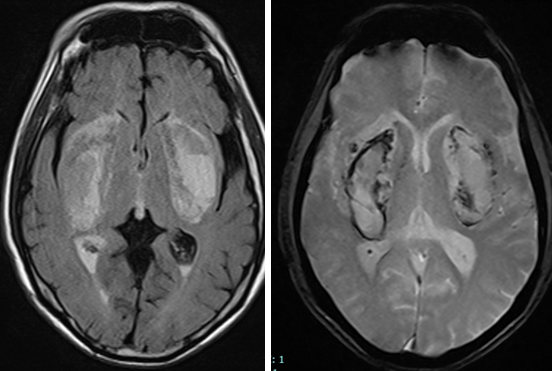

Hình ảnh tổn thương nhồi máu, chảy máu nhân bèo hai bên ở người bệnh ngộ độc Methanol do uống cồn giả pha nướcHình ảnh tổn thương nhồi máu, chảy máu nhân bèo hai bên ở người bệnh ngộ độc Methanol do uống cồn giả pha nước

Kết quả chụp cộng hưởng từ sọ não cho thấy tổn thương nhồi máu, hoại tử, chảy máu nhân bèo hai bên – đây là dạng tổn thương não điển hình do ngộ độc methanol. Người bệnh dù được hồi sức tích cực, lọc máu, thở máy nhưng tình trạng rất nặng, người bệnh hôn mê sâu, nguy cơ cao đối mặt với tình trạng sống thực vật.